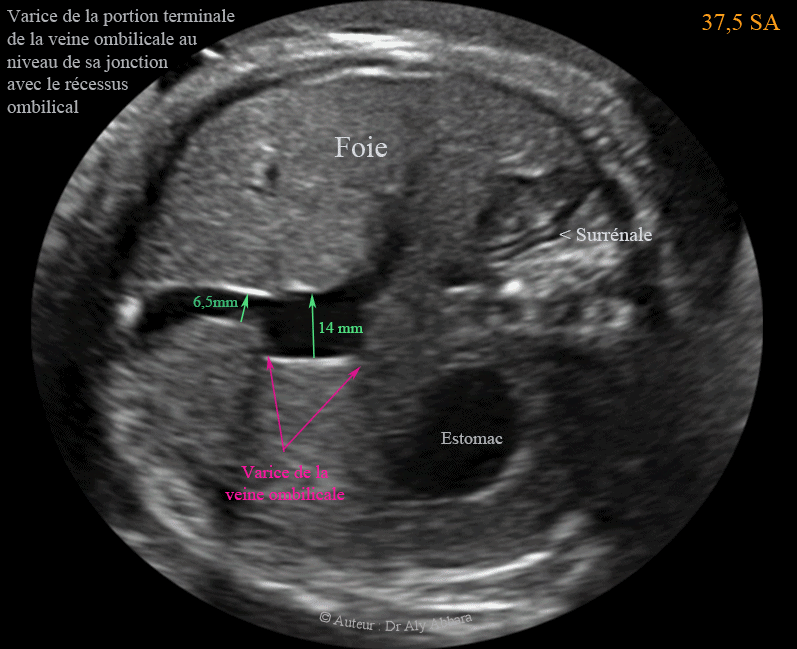

Varice proximale de la veine ombilicale intra-abdominale  - دوالي الوريد السري داخل بطن الجنين

• Vidéo échographique montrant la présence d'une varice (dédoublement du diamètre) de la veine ombilicale intra-abdominale au niveau de sa portion près terminale (juste avant le récessus ombilical de cette veine).

• Grossesse de 37,5 SA

• Les varices de la veine ombilicale intra-abdominale représentent 4 % des anomalies du cordon. Dans les varices de la veine ombilicale, la dilatation (ectasie) localisée de la veine ombilicale intra-abdominale est supérieure à 50 % du diamètre de la partie non dilatée de cette veine.

• Les varices de la veine ombilicale intra-abdominale peut être proximales (juste après l'insertion du cordon ombilicale à la paroi abdominale) ou sur n'importe quelle portion de la partie abdominale de cette veine.

• Les varices de la veine ombilicale intra-abdominale peuvent être isolées, généralement de bon pronostic, ou associées, dans 11 à 12 % à d'autres malformations (en particulier cardiaque), dont 10 % des cas sont des anomalies chromosomiques.